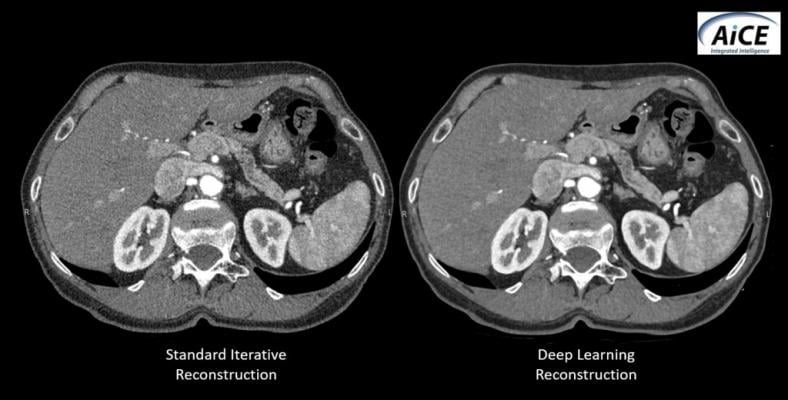

February 27, 2019 — Canon Medical Systems recently introduced AiCE (Advanced intelligent Clear IQ Engine), a deep convolutional neural network (DCNN) image reconstruction technology for computed tomography (CT). AiCE uses deep learning technology to differentiate signal from noise so that it removes noise while it preserves true signal.

With the AiCE deep learning approach, the DCNN is trained in the factory using perfect high-quality target data from real patient datasets. This patient data is extensively processed with advanced model based iterative reconstruction (MBIR), which provides optimal image quality and improved spatial resolution.

Following training and validation, the AiCE DCNN is then implemented into the CT scanner that allows for reconstruction speeds fast enough for busy clinical environments.